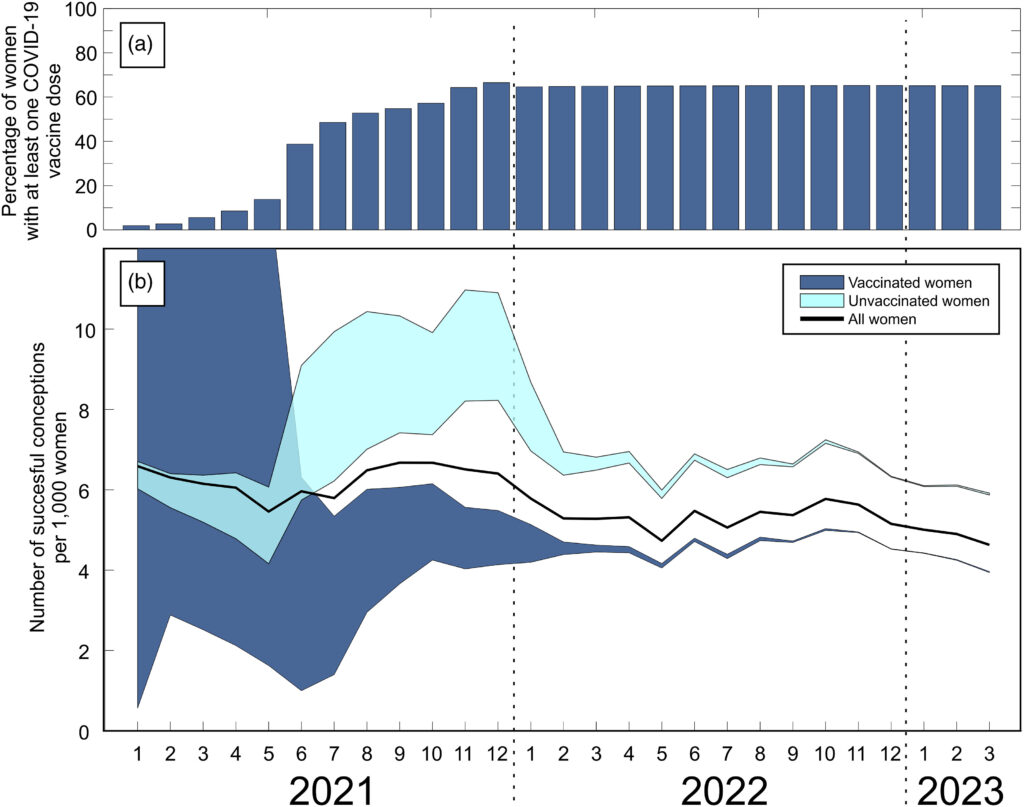

チェコ共和国における18〜39歳の女性の月次COVID-19ワクチン接種率および出生データは、2021年1月から2023年12月までの期間に取得されました。妊娠前ワクチン接種済みおよび未接種女性それぞれについて、1000人の女性あたりの月間SC(妊娠(SC)成功率(すなわち9か月後に出生に至る))数と、18歳から39歳の全女性について千人あたりの月間SC数を算出しました。

チェコ共和国では、SC以前にCOVID-19ワクチン接種を受けた女性のSC率は、接種していない女性に比べて大幅に低かった。(2025, Manniche)